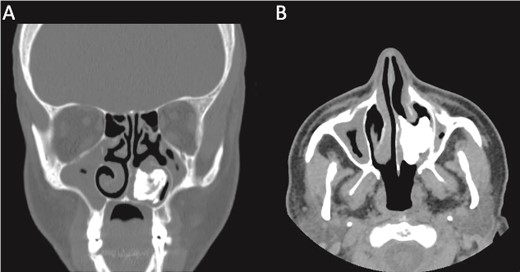

This presentation was clinically suggestive of left-sided rhinolith. Hence, a CT scan was obtained, which showed a well-defined expansile heterogeneous calcified/ossified lesion occupying the inferior aspect of the left nasal cavity measuring 2.5 × 3 × 2.1 cm (craniocaudal × anteroposterior × transverse). Also, the lesion was expanding the nasal cavities with bone remodeling of the medial wall of the maxillary sinus with remodeling and superior displacement of the left inferior turbinate (Fig. 1). These findings were highly suggestive of rhinolith; therefore, the patient was scheduled for a left endoscopic rhinolith removal. Intraoperatively, a giant, calcified nasal lesion was noticed and removed from the left nasal cavity, which was attached to the inferior and middle turbinates (Fig. 2). Furthermore, a biopsy from the lesion was taken for histopathological analysis, showing calcification with fibrin and hemorrhage. These findings confirmed the diagnosis of left nasal rhinolith, and the patient was discharged with no complications. Six months after the procedure, A the patient presented to the clinic with no signs of recurrence, and her endoscopic examination revealed clear nasal cavities (Fig. 3).

A CT scan with (A) coronal view and (B) axial view showing a well-defined expansile heterogeneous calcified/ossified lesion occupying the inferior aspect of the left nasal cavity.